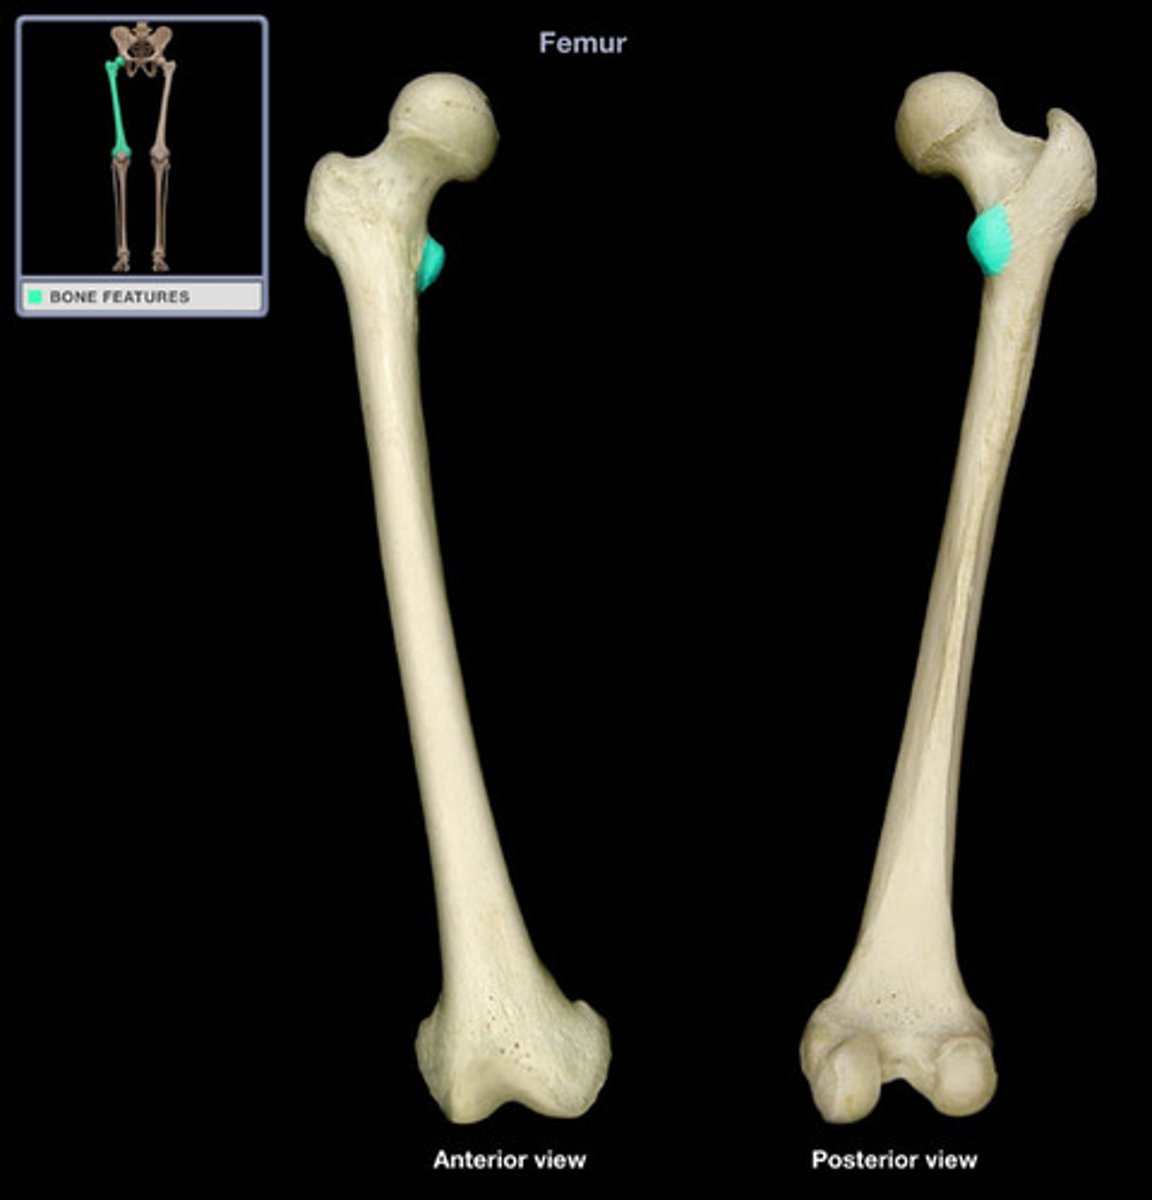

Femur

Lesser Trochanter